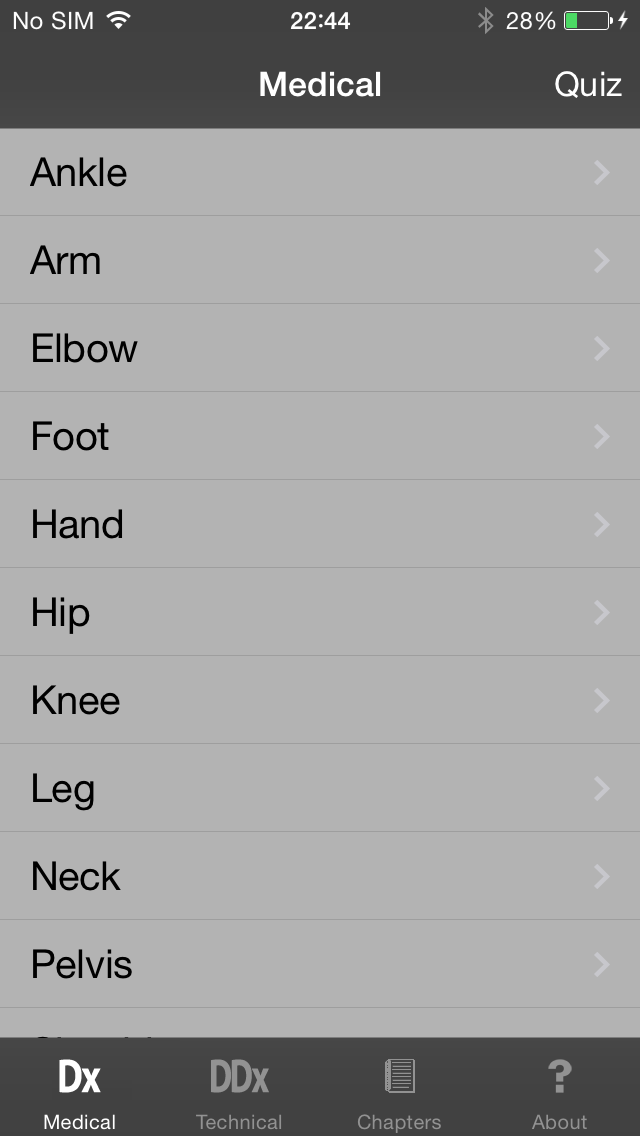

Скриншоты